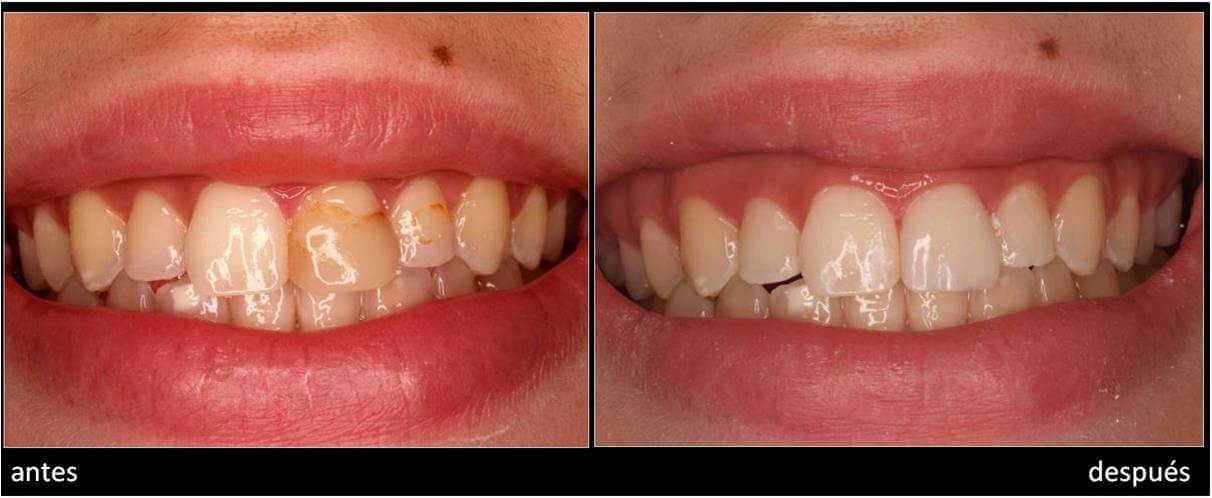

ESTÉTICA.INCISIVO CENTRAL SUPERIOR